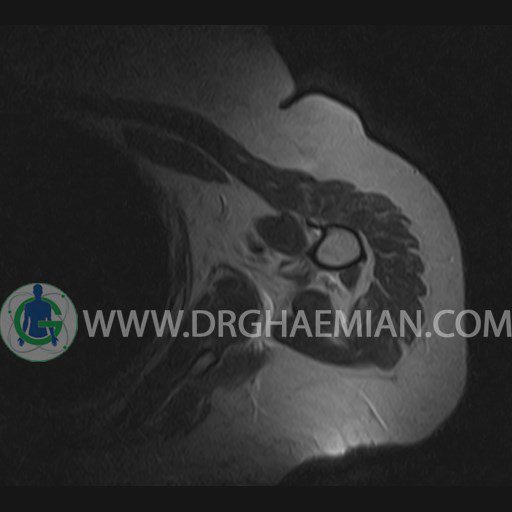

ام آر آی آتروفی عضلانی کتف بیمار

ام ار آی کتف یک روش تصویربرداری است که به وسیله آهنرباهای قدرتمند از قسمت کتف تصاویری ایجاد می کند. این نوع تصویربرداری از تشعشعات استفاده نمی کند. در این کیس آتروفی عضلانی کتف به همراه پارگی تاندون بالاخاری، بورسیت ساب دلتوئید و افیوژن مفصل دیده می شود.

– Complete tearing of supraspinatus tendon with grade 2 retraction and muscle atrophy

– AC joint hypertrophy with subacromial – subdeltoid bursitis

– Glenohumeral joint effusion

are seen.